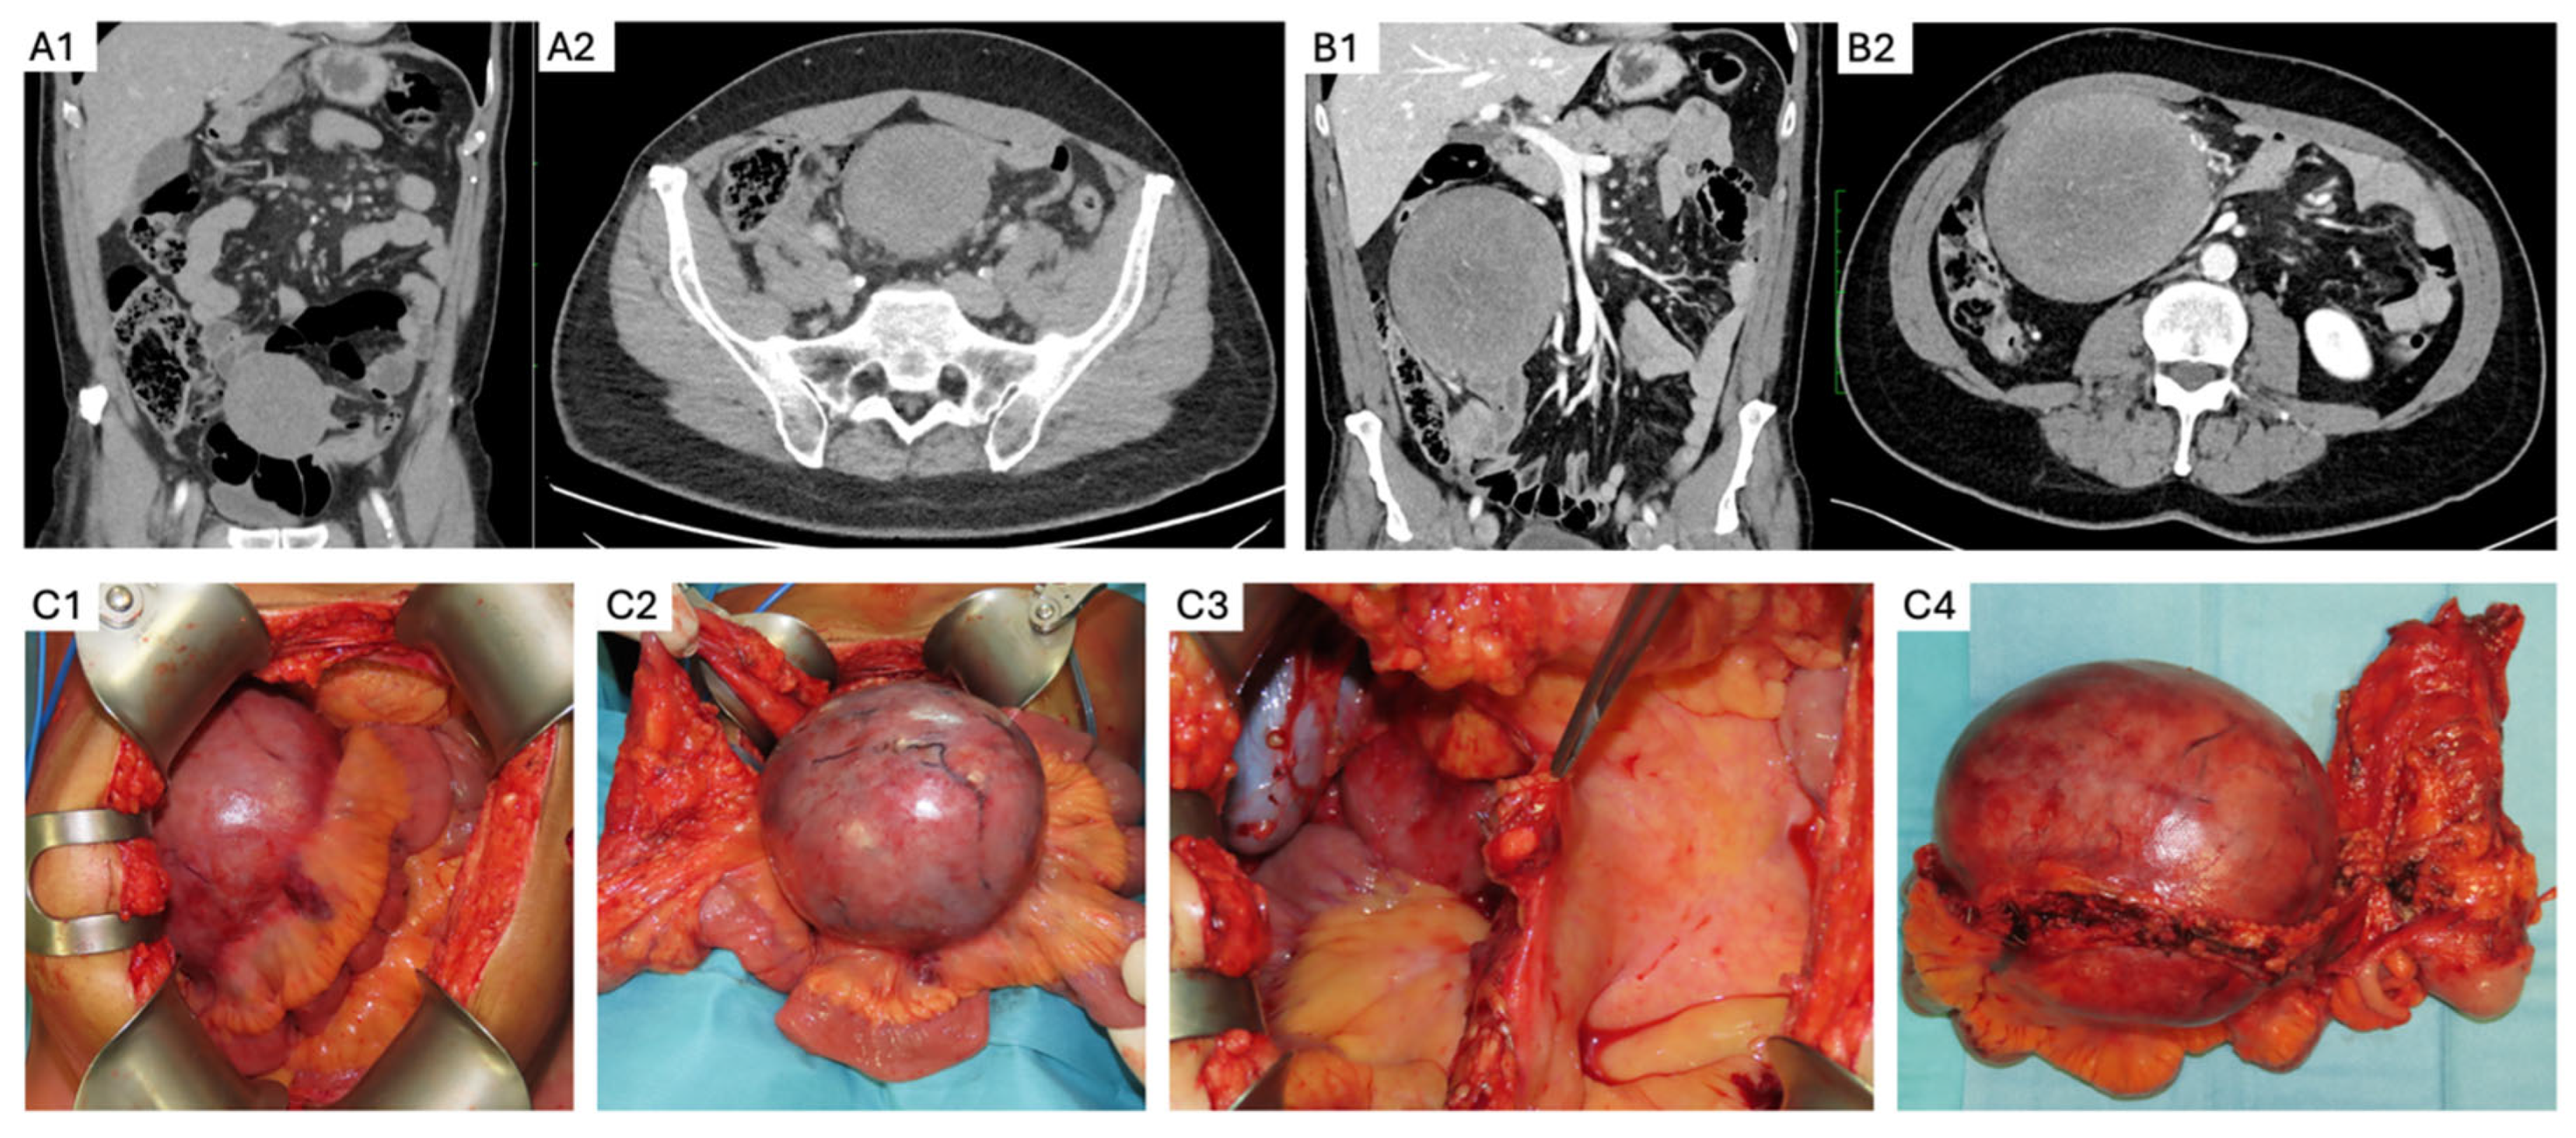

3. Abdominal Wall DTs

- Elective resection as primary treatment. In patients with resectable primary disease and low anticipated morbidity, complete macroscopic clearance can be achieved (Figure 3) with favorable operative outcomes in specialist centers [62]. When assessing resectability, key considerations include mesenteric vasculature involvement, anticipated length of small bowel and/or colonic resection, risk of short gut syndrome, and additional visceral involvement. The potential for future tumor growth and associated complications must also be carefully weighed [20,59]. In case of prior incomplete resection and evidence of residual disease, AS is recommended due to the possibility of an indolent course [63].